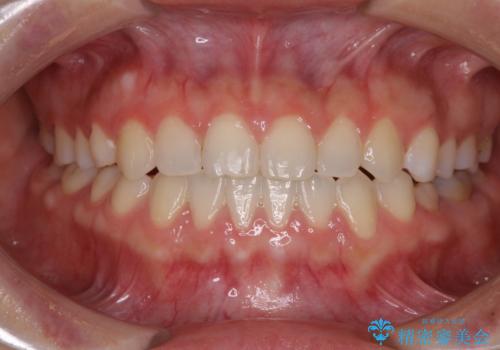

治療期間中は奥歯がほとんど咬めない状態が続き、食事に大変苦労されました。

最終的には隙間もしっかりと閉じ、奥歯も咬みやすい状態でしあげることができました。